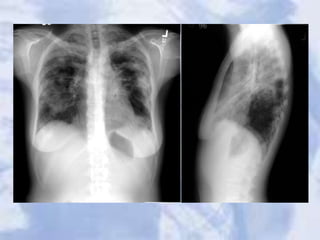

Case 1

A single, 3cm relatively thin-walled cavity is noted in the left

midlung. This finding is most typical of squamous cell carcinoma

(SCC). One-third of SCC masses show cavitation